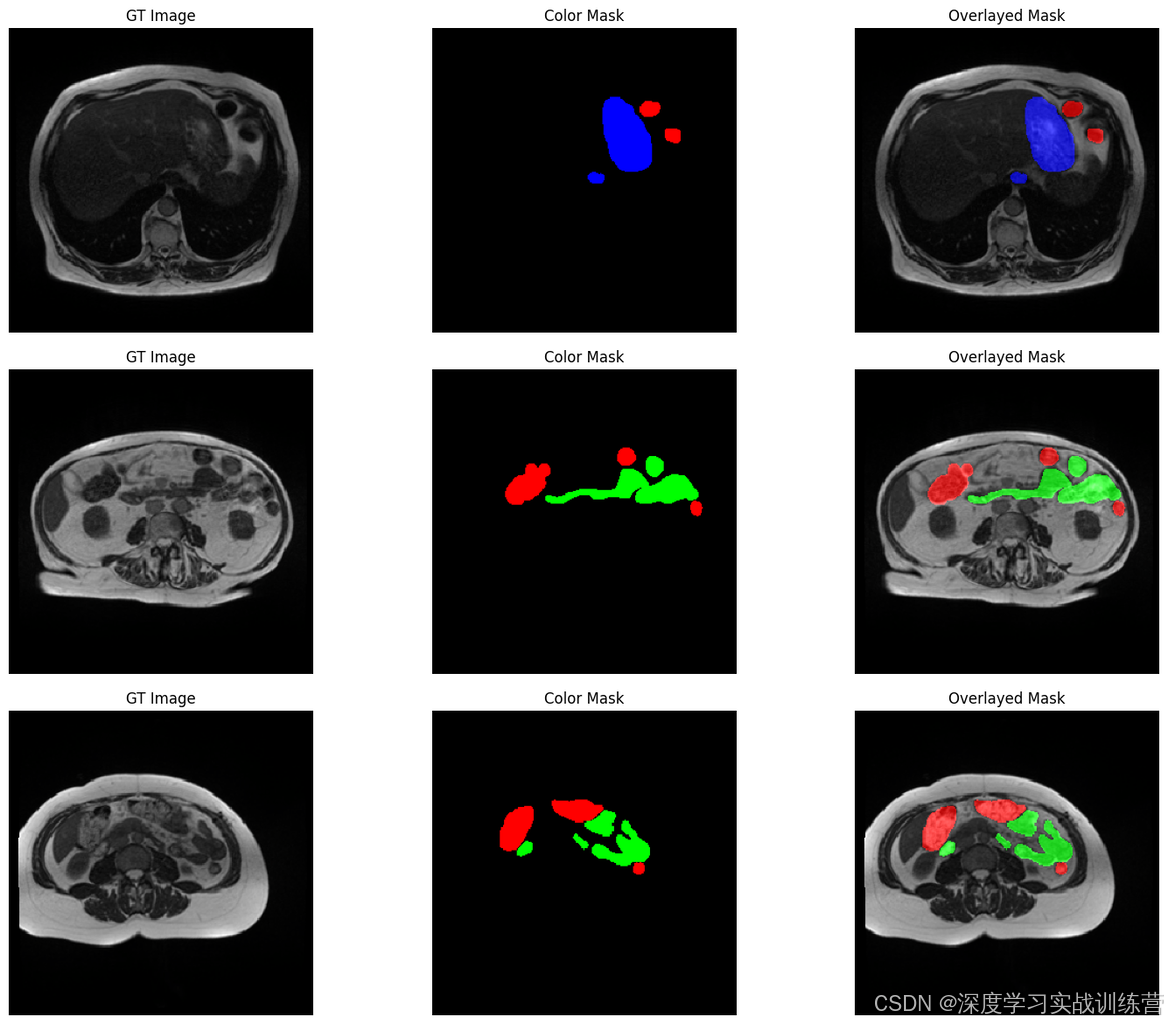

本项目基于A052-SegFormer模型实现医学影像图像分割,旨在提供一种高效且精准的分割方案以满足临床和研究中的图像处理需求。医学影像分割是医疗领域中的一个关键任务,它能够辅助医生进行疾病的精准诊断和分析,例如器官或病灶的定位与形态判断。传统的分割方法依赖手工设计特征或简单的阈值分割,无法处理复杂的结构和形态,而深度学习模型凭借其强大的特征提取和学习能力,可以自动从数据中提取多层次的信息表示。本项目中采用了SegFormer模型,这是一种基于Transformer的图像分割架构,结合了卷积神经网络和Transformer的优点,通过多尺度特征提取和自注意力机制能够有效捕捉医学图像中不同尺度下的特征信息,从而提升分割性能。该模型使用轻量化设计,具有较低的计算开销和内存需求,非常适合应用于资源受限的场景,如实时诊断系统和便携式医疗设备。项目的主要目标是验证SegFormer在医学图像数据集上的分割性能,并通过对比实验和可视化展示其在精度和效率方面的优势,为实际应用提供理论支持和算法参考。